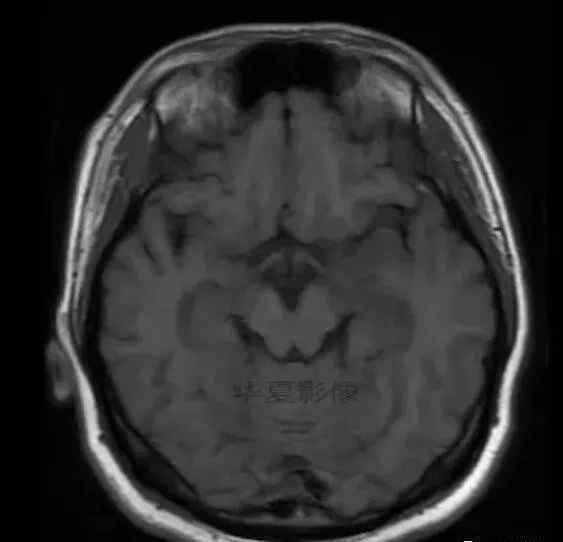

男,25岁,6天前意外感冒,现在发烧。他的体温超过39.0℃,他的呕吐物不是喷射状的。他的呕吐物是胃里的东西。

1.左侧颞叶、海马和岛叶T1WI信号低,T2WI信号高

2.病变没有明显的边界

3.占用效果不明显

4.豆状核不受影响